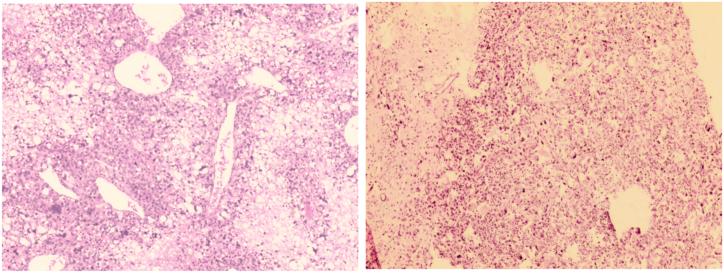

we report a case of primary pleomorphic liposarcoma of the left distal femur of a twelve-year-old female. The patient presented with a painful lower thigh swelling, not responding to analgesics. Imaging studies were done and showed a lesion extended across the distal physeal plate laterally and centrally with scattered lesions medially. Histologically, the tumor showed a uniformly pleomorphic liposarcomatous pattern with extensive necrosis. Genetic analysis showed frequent mutations in LATS2, CREBBP, and SMAD2 genes in addition to deletions and amplifications in different genetic pathways. Two cycles of MAP chemotherapy were completed before tumor excision and total left knee replacement, followed by two other MAP cycles postoperatively. Multiple lung metastases were detected on chest CT 10 months postoperatively. The patient died 13 months postoperatively.

我们报告一例12岁女性左股骨远端原发性多形性脂肪肉瘤。患者表现为下大腿疼痛性肿胀,对镇痛药无反应。进行了影像学检查,显示病变横向和中央延伸穿过远端骨骺板,内侧有散在病变。组织学上,肿瘤呈现一致的多形性脂肪肉瘤模式,伴有广泛坏死。基因分析显示,除了不同基因途径中的缺失和扩增外,LATS2、CREBBP和SMAD2基因频繁突变。在肿瘤切除和全左膝关节置换术前完成了两个周期的MAP化疗,术后又进行了另外两个周期的MAP化疗。术后10个月胸部CT检测到多处肺转移。患者术后13个月死亡。